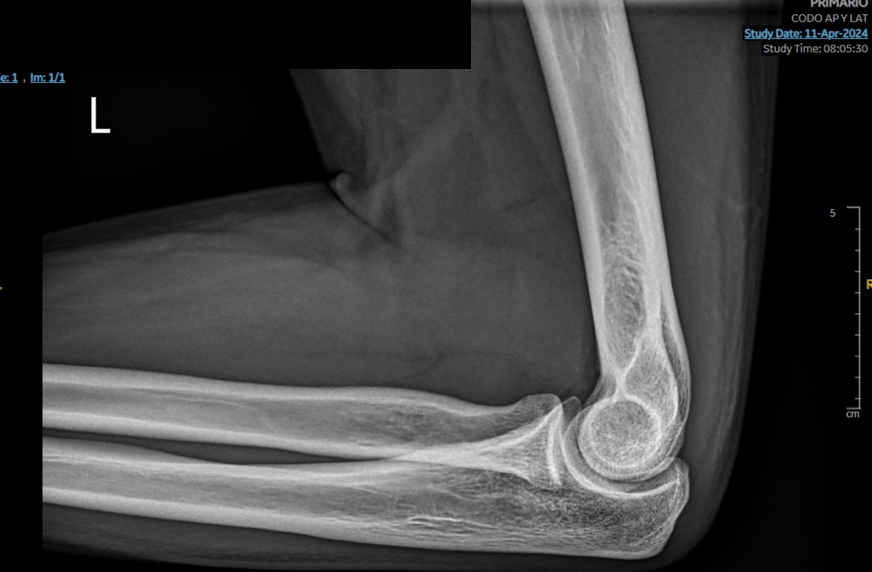

• Radiografía de codo en abril de 2024 donde no se aprecian alteraciones óseas ni de partes blandas.